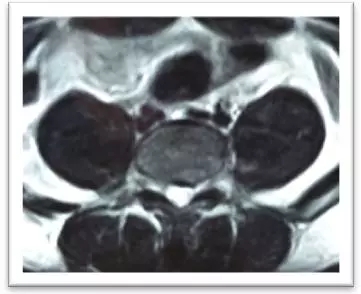

(術(shù)中)

4月8日,在局麻下,劉志安副院長(zhǎng)親自實(shí)施了腰5/骶1椎間盤(pán)突出癥經(jīng)脊柱內(nèi)鏡髓核摘除術(shù),術(shù)中摘除了大塊脫出髓核組織。